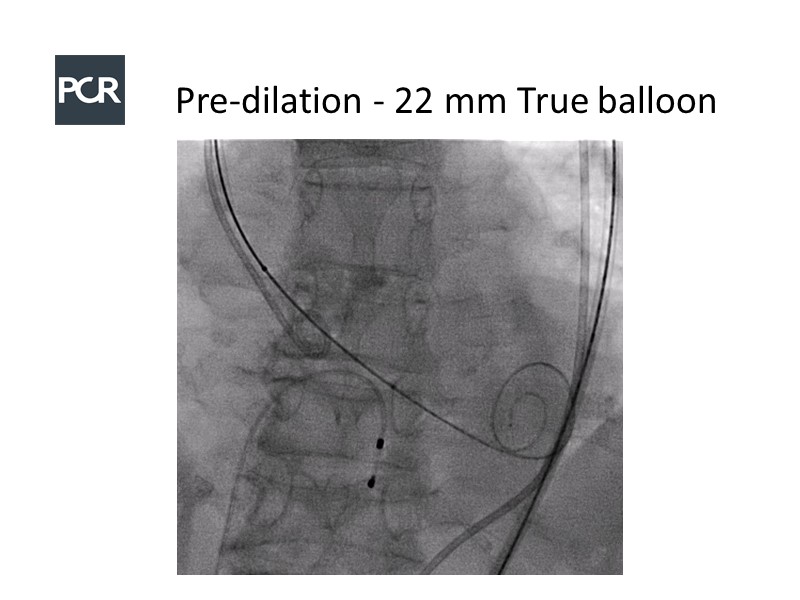

In this session, a panel of experts introduce the VitaFlow TAVI system, a good option for patients with complex anatomies. They also present the five-year results of VitaFlow in severe aortic stenosis.

- To learn about the VitaFlow TAVI system and the five-year results of VitaFlow in severe aortic stenosis